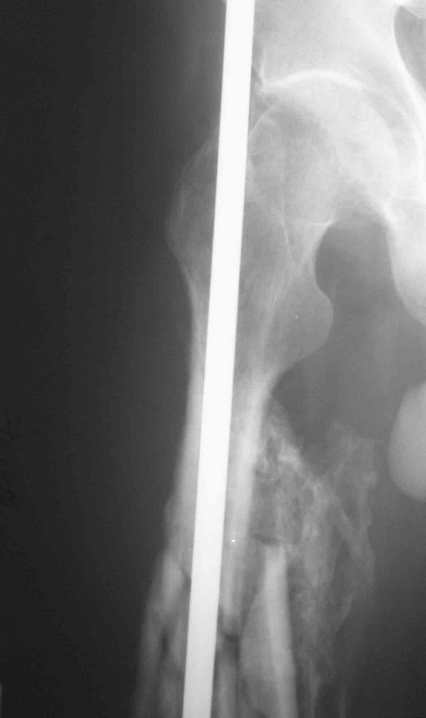

Иллюстрации к сообщению

Уважаемый Антон.Исходя из Вашего материального положения!! и наличия хорошего, грубого омозоления, равности длины конечностей и судя по снимкам не очень выраженной антекурвации, но выраженной контрактуры коленных суставов: чтоб не упустить время разработки суставов и активизировать больного, необходимо справа удалить стержень, рассверлить канал и произвести ЗИМО более толстым неблокир. стержнем т.к. на этом уровне можно получить устойчивый остеосинтез, после чего активизировать и дозированная, упорная ЛФК, а дальше после восстановления функции ,время покажеть.

Cyдя по представленным рентгенограммам оба бедра консолидированы. Необходима активная разработка движений в коленных суставах. Хотелось бы увидеть фотоснимки больного ( нижних конечностей спереди и сбоку). Если стержень мешает разработке движений то его надо удалить.